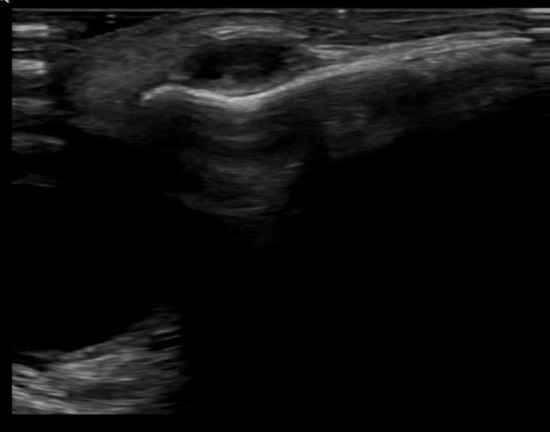

Se realiza ecografía de partes blandas en la que se objetiva lesión quística de 8 x 9 mm de tamaño.

La paciente persiste asintomática, pero en torno a los 22 meses de edad, impresiona de aumento de tamaño, por lo que se solicita ecografía de control, en la que se objetiva la persistencia de la lesión quística con similares características, pero con aumento de tamaño a 13 x 10 mm (Figura 1).

Figura 1. Ecografía